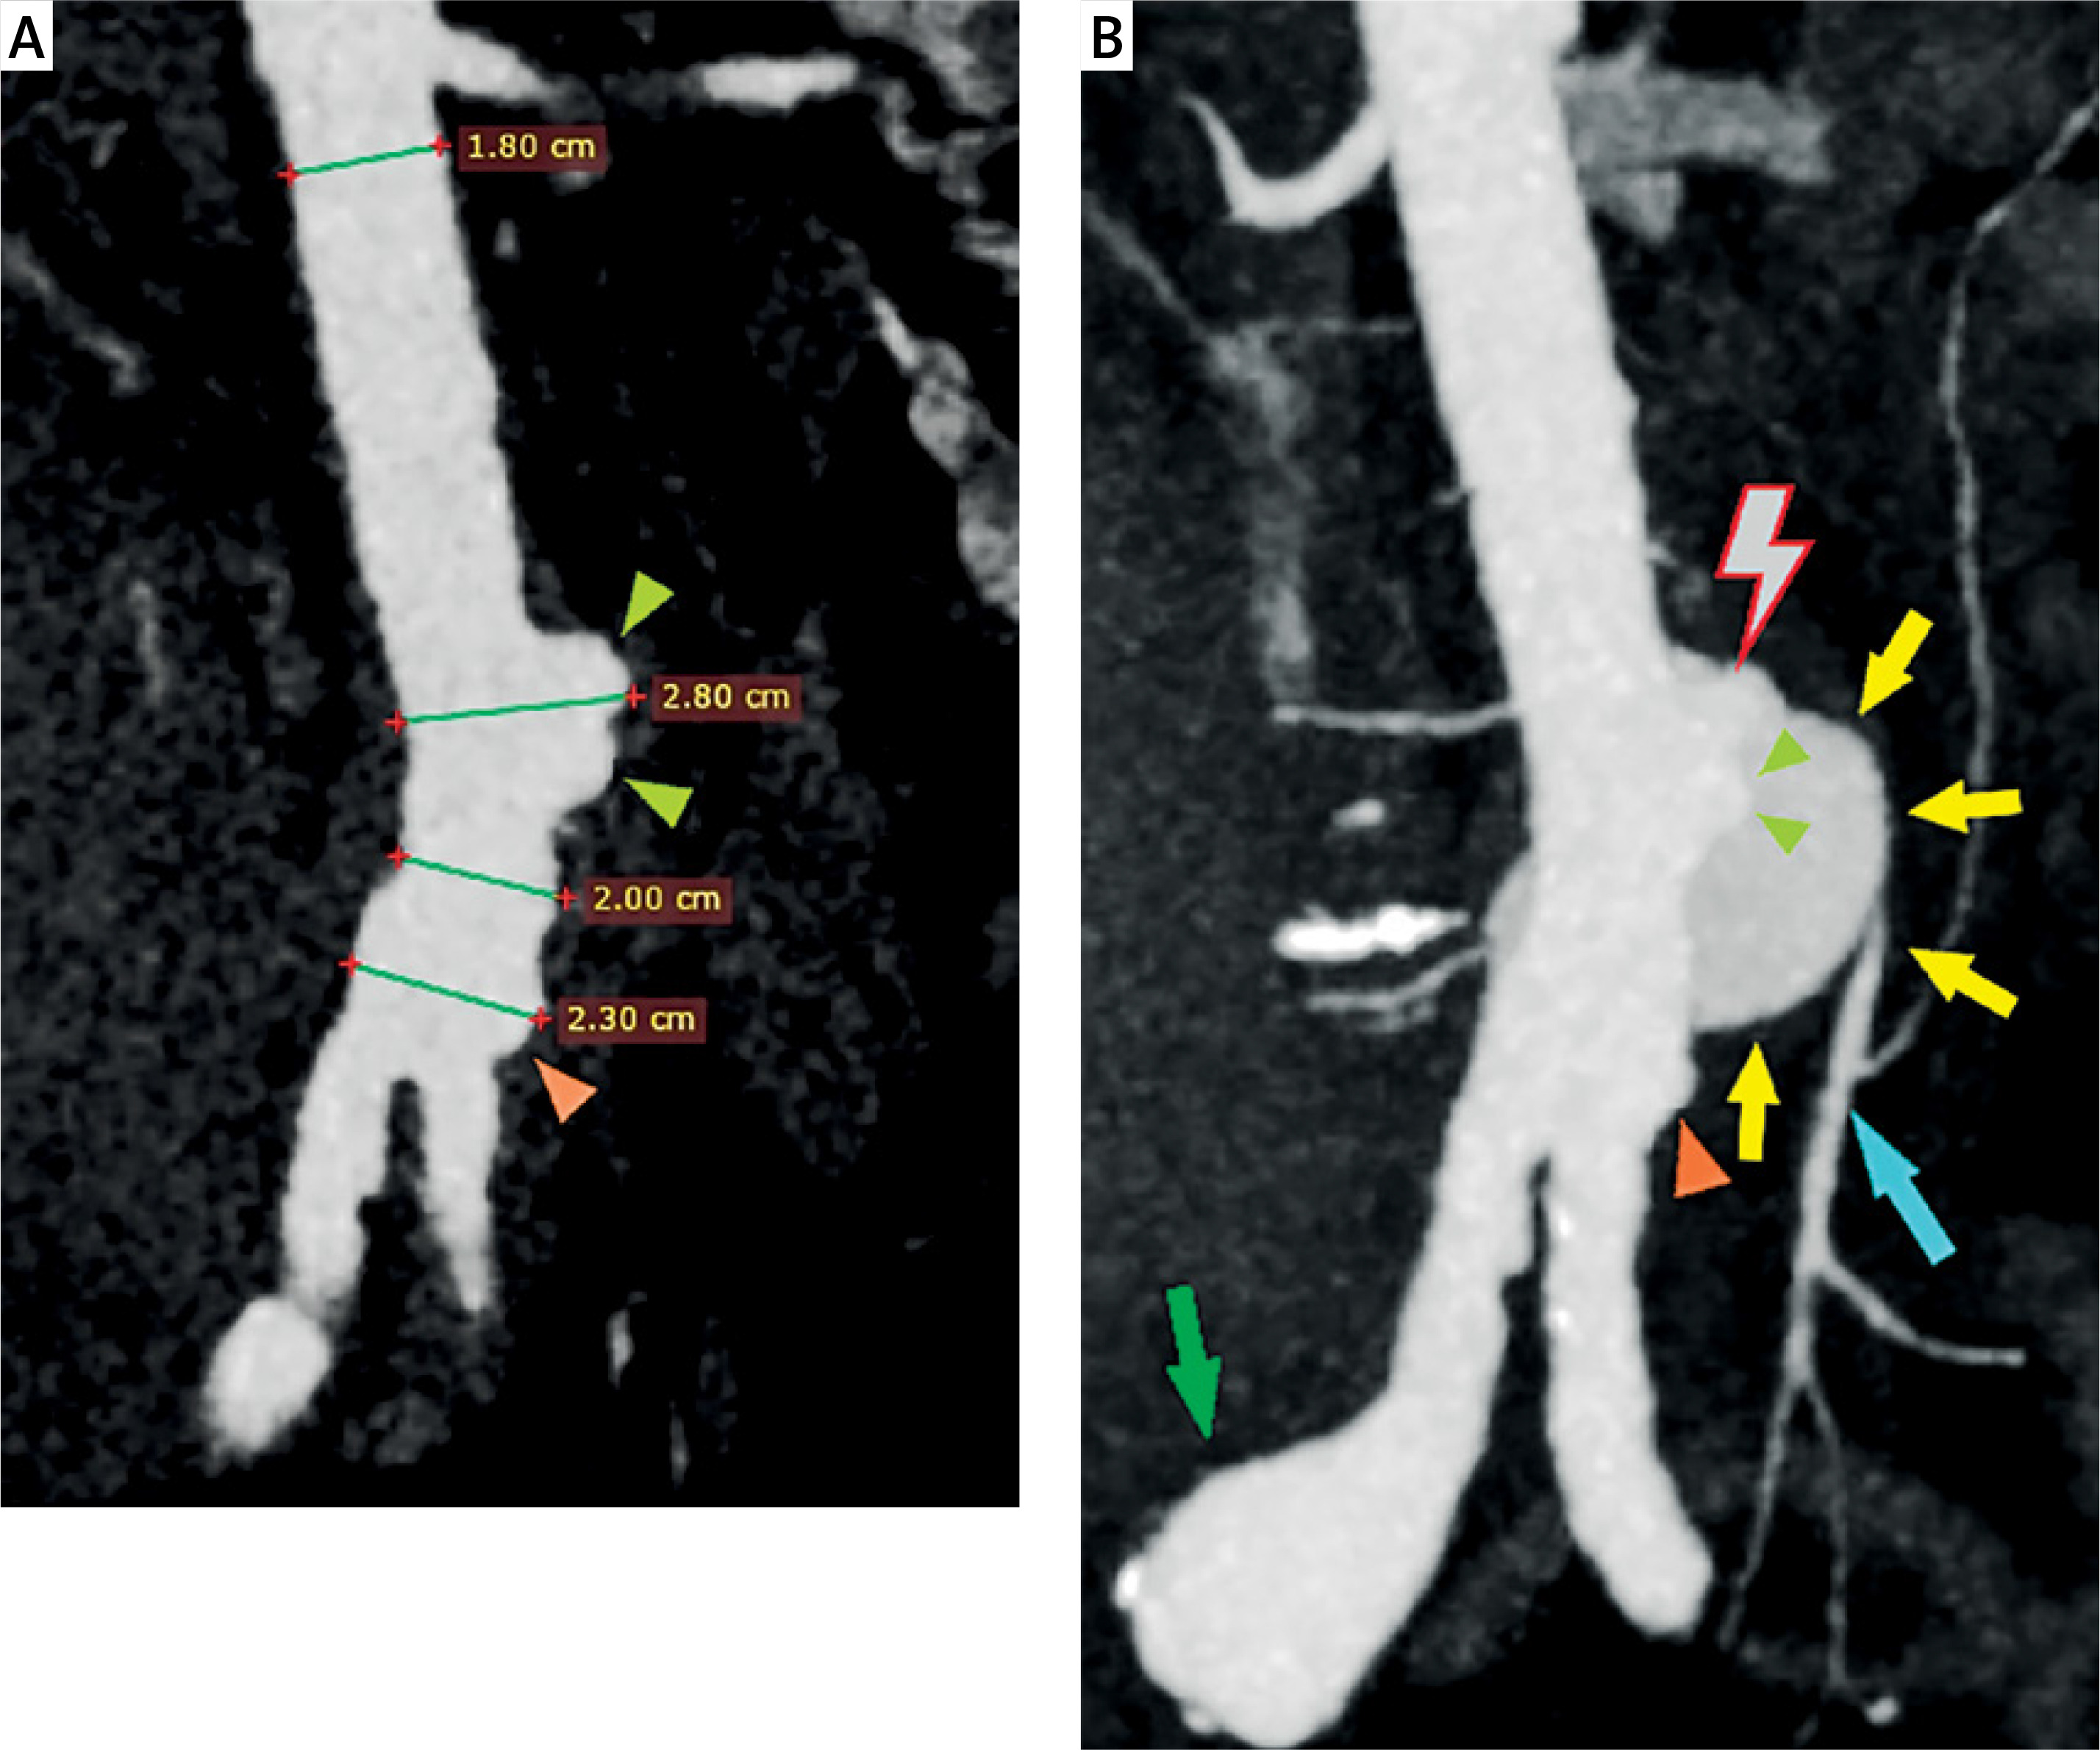

Figure 2

Computed tomography angiography (CTA) revealed an aortic rupture with gross extravasation of contrast media, 3.7 cm below the renal arteries, leading to a pseudoaneurysm and a large retroperitoneal hematoma (A – MPR reconstruction, sagittal view: red lightning bolt: aortic rupture, yellow arrows: aortic pseudoaneurysm, green arow: right common iliac artery aneurysm, B – Axial view: red lightning bolt: aortic rupture, yellow arrows: aortic pseudoaneurysm, light green arrowheads: focal aortic dilatation, light blue arrows: large retroperitoneal hematoma)